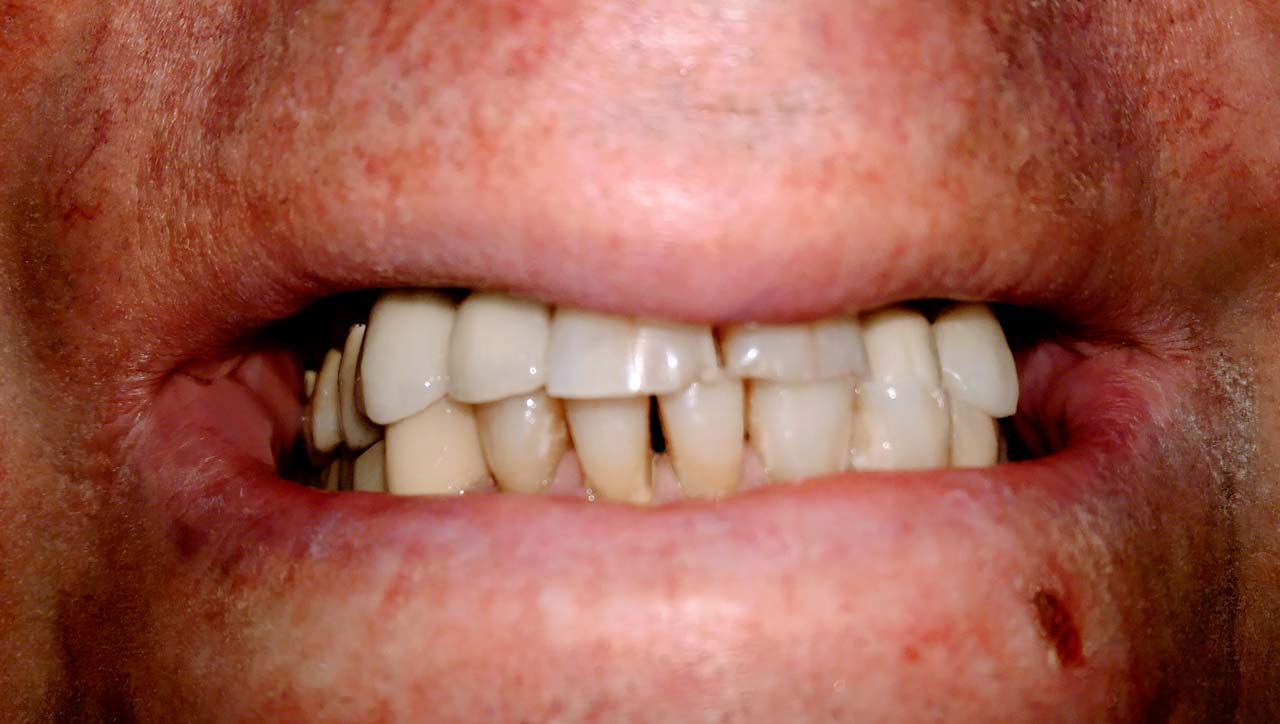

Teljes szájüregi rehabilitáció két lépésben

Ismét egy teljes szájüregi rehabilitáció két lépésben. Először az alsó fogak lettek kihúzva és azonnal implantálva, híddal ellátva, majd később a felső. IHDE svájci azonnal terhelhető implantátumok és cirkónium hidak. Dr. Kelemen Péter és a Symbion Fogtechnika közös munkája.